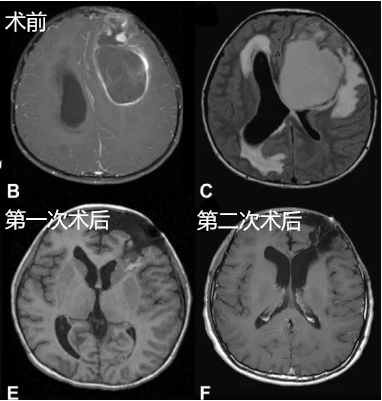

這樣一個(gè)巨大的室管膜瘤盤踞在10歲的杰克腦中,令人觸目驚心。連續(xù)三周的精神萎靡、運(yùn)動(dòng)遲緩以及間歇性的嘔吐,讓杰克深受折磨。然而,當(dāng)父母一看到這幅驚人的影像時(shí),更深的絕望籠罩在一家人心中:孩子還能活下去嗎?

巨大的腫瘤已經(jīng)造成嚴(yán)重的占位效應(yīng)和腦積水,從影像上也可以看到廣泛的室周和瘤周水腫,眼底檢查圖像更是顯示明顯的乳頭水腫,這些都為手術(shù)帶來巨大的困難。

所幸,杰克一家的主刀醫(yī)生為Rutka教授,為了盡可能全切腫瘤,并保留杰克的神經(jīng)功能,Rutka教授制定了一套更為個(gè)體化的治療方案,包括分階段的手術(shù)及術(shù)后放療鞏固效果,提升孩子預(yù)后的同時(shí)延緩復(fù)發(fā)。

很快,第一次手術(shù)正式開始,并成功切除了腔底部向側(cè)腦室方向的部分腫瘤,取得的組織病理顯示為間變性室管膜瘤。第二次手術(shù),Rutka教授完成大面積的腫瘤切除。為了不損傷重要神經(jīng)血管,保留杰克的神經(jīng)功能,教授并未強(qiáng)行全切,因?yàn)閷?duì)于神經(jīng)外科手術(shù)來說,是否全切并非評(píng)判手術(shù)成功與否的標(biāo)準(zhǔn),重要的是術(shù)者在切除范圍和保障功能之間的博弈。

為了進(jìn)一步鞏固手術(shù)效果,Rutka教授為杰克制定了后續(xù)的放療方案,這一縝密的治療策略無疑為杰克帶來了良好的生活質(zhì)量,他的最后一次隨訪中也并未發(fā)現(xiàn)腫瘤復(fù)發(fā)的跡象。